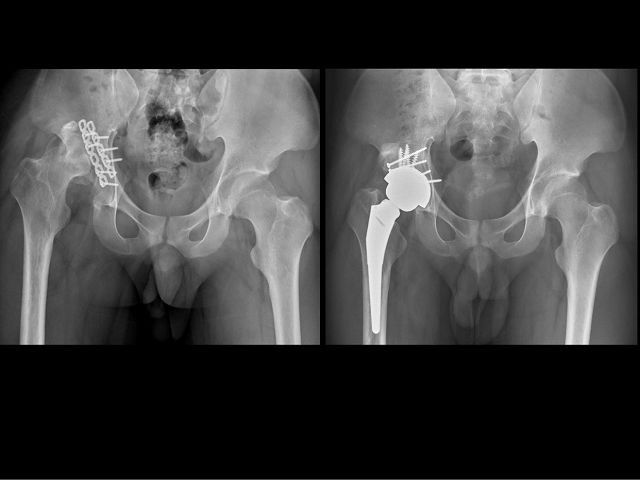

為讓男大生恢復走路重拾生活品質,李芳材、楊鎮源協同關節重建科主任蕭敬樺共同擬定手術計畫。蕭敬樺醫師解釋,首先為病人置換人工髖關節考量其髖關節因錯位有嚴重骨缺損,髖臼就像破了洞的碗,醫師透過院內骨骼銀行異體骨移植填補破洞後,再置換人工髖關節到正確位置,讓髖關節恢復功能同時也一併改善長短腳。

第2階段由楊鎮源醫師施以神經鬆解手術,將受傷的坐骨神經與周圍嚴重沾黏的纖維化組織仔細分開,達到神經減壓目的,緩和右腳持續電麻感。最後進行肌腱轉移手術,將脛後肌肌腱繞道固定至足背骨頭,加強腳掌背屈的力量,改善垂足。階段性的關節重建、神經鬆解、肌腱轉移手術,有效地改善了病人的麻痛感,恢復走路能力可自理生活,目前只要定期回診即可。